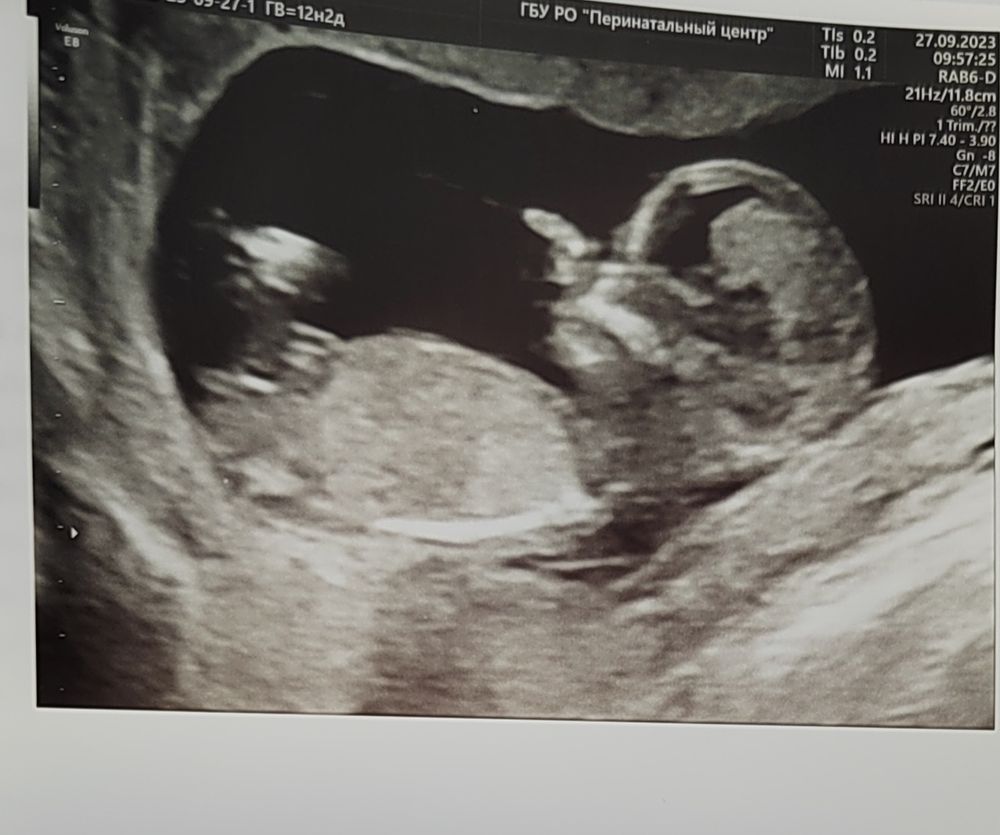

Мне вчера Тё Сергей определил на 12 недели пол))) Я была восхищена его мастерством. Он сказал в это время у мальчиков и девочек выглядит одинаково бугорок, но смотрит В разные стороны (где то на 30 градусов разница). По анализу нипт совпал пол у меня. Определить на первом скрининге можно, но нужен аппарат хороший и врач внимательный.

Юлия, если по градусам смотреть, то примерно девочка будет. На мальчика не похоже. Это если по градусам судить

Юлия, у меня первая мысль была что девочка. Но я совсем в этом не разбираюсь. Мне кажется на некоторых снимах ножками закрыто🤭